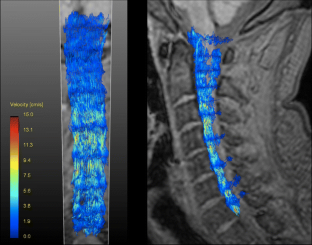

In healthy volunteers the main CSF flow component was evenly distributed across the anterior and anterolateral subarachnoid space extending from the craniocervical junction throughout the entire cervical spinal canal. (MPG 10050 kb)